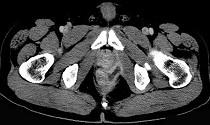

问题 男,28岁,高热,肛门坠胀,频有便意,直肠指诊时触及直肠粘膜下饱满,柔软,压痛的肿块,CT检查如图,诊断为 ( )

选项 A.直肠癌 B.直肠炎性息肉 C.直肠粘膜下脓肿 D.直肠绒毛状腺瘤 E.直肠粘膜下瘘

答案 C